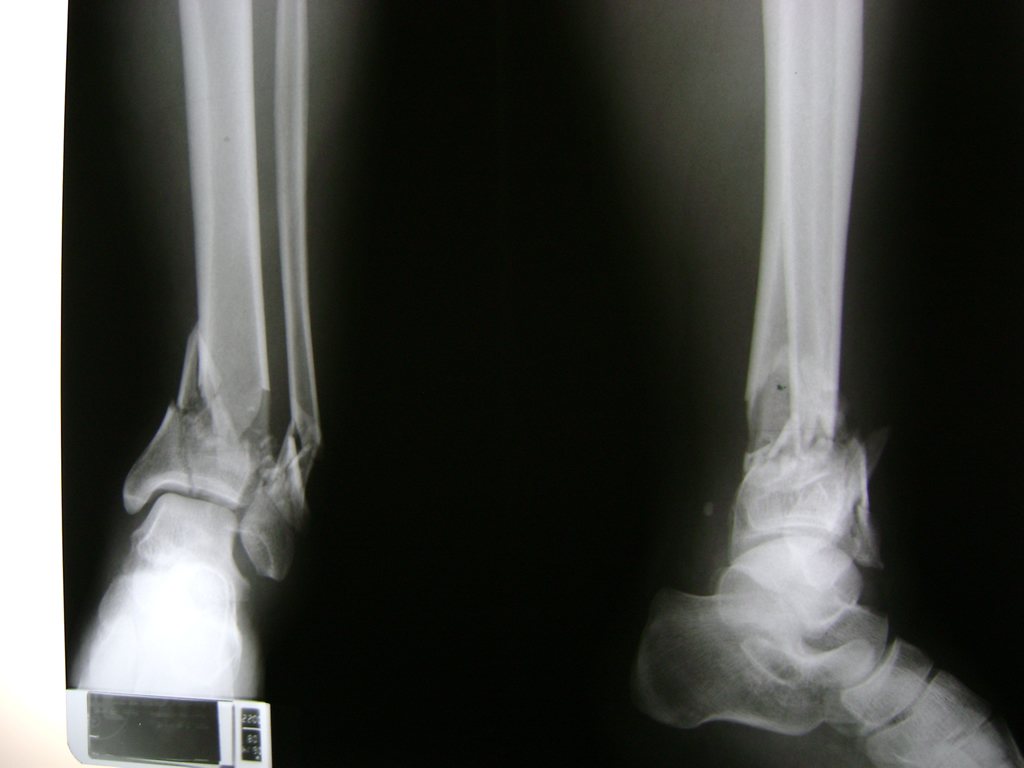

Una fractura de tobillo es la rotura de uno o más de los huesos del tobillo. Estas fracturas pueden ser:

• Parciales (el hueso está sólo parcialmente fisurado, no del todo).

• Completas (el hueso está perforado y está en 2 partes).

• Producirse en uno o ambos lados del tobillo.

Algunas fracturas de tobillo pueden requerir cirugía si:

• Los extremos de los huesos están desalineados entre sí (desplazados).

• La fractura se extiende hasta la articulación del tobillo (fractura intra-articular).

• Los tendones o ligamentos (tejidos que sujetan los músculos y los huesos entre sí) están rotos.

• El médico cree que sus huesos probablemente no sanen apropiadamente sin cirugía.

• El médico considera que la cirugía puede permitirle una recuperación más rápida y confiable.

• En los niños, la fractura involucra la parte del hueso del tobillo donde el hueso está creciendo.

Cuando se necesita cirugía, es probable que esta implique el uso de clavijas de metal, tornillos o placas para sostener los huesos en su lugar mientras la fractura se consolida. Los elementos de soporte pueden ser temporales o permanentes.